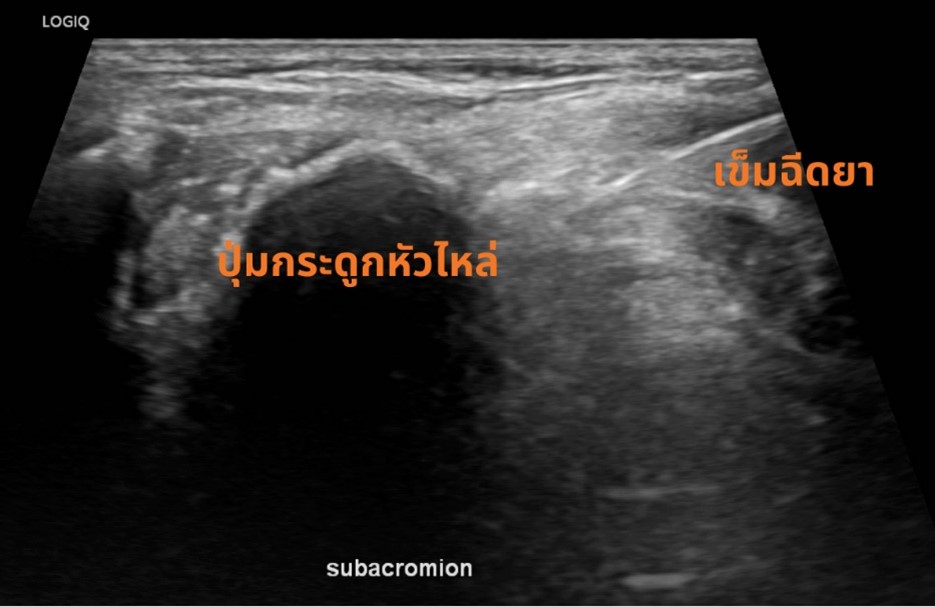

การรักษา หากอาการไม่มาก สามารถใช้การทำกายภาพบำบัด ออกกำลังกาย ร่วมกับเครื่องมือทำกายภาพ เพื่อเพิ่มพิสัยการขยับของข้อให้ได้มากขึ้น และหากอาการรุนแรง ที่ VASU pain management เรามีวิธีการรักษาโดยใช้การฉีดกลูโคสเข้าไปบริเวณข้อไหล่ และเส้นเอ็น เพื่อทำให้ผังผืดที่ติดนั้นคลายออก (Hydro dissection) ซึ่งการทำหัตถการนี้จะใช้อัลตราซาวน์ในการนำทางของเข็ม ทำให้เราสามารถระบุตำแหน่งได้ชัดเจน ปลอดภัย และมีประสิทธิภาพมากยิ่งขึ้น โดยหากใช้วิธีดังกล่าว จะสามารถทำให้ผู้ป่วยหายจากภาวะไหล่ติดได้เร็วมากยิ่งขึ้น